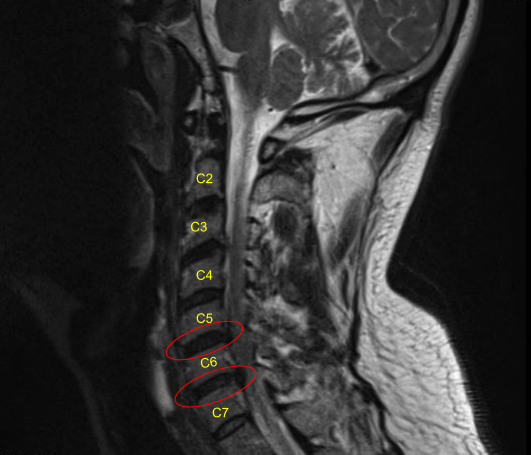

Supraplatysmal dissection was performed to allow mobility of the incision. Deep dissection was performed between the strap muscles and sternocleidomastoid. The anterior spine was reached. Hemostat was used to check the level and found to be at C5-C6.

Further dissection was performed distally as well as proximally to open the area. A needle was used in the disc space to confirm the level and found to be C5-C6 and saved. The disc was marked and the distal disc was also marked at C6-C7. The longus colli was raised on either side of C5, C6, and C7 to expose the body as well as the disc.

Skyline retractors were used. Caspar pin were passed into C7 and C6 to allow distraction of C6-C7. Discectomy of C6-C7 was performed using curette and Kerrison. Thorough foraminotomy of bilateral C7 was performed with the use of Kerrison punches Number 1 and 2.

The disc holder was removed. Now, the C7 Caspar pin was removed and inserted into C5. Distraction of C5-C6 was performed using the Caspar distractor. Discectomy was performed using curette and Kerrison #1 mm and 2 mm. PLL was excised and osteophytes were removed. Thorough foraminotomy of bilateral C6 was performed with the use of Kerrison punches number 1 and 2.